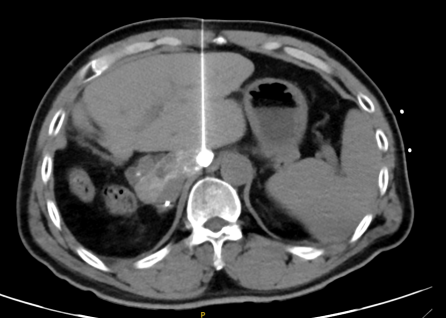

再行经皮穿刺无水酒精消融彻底毁损病灶

手术过程: